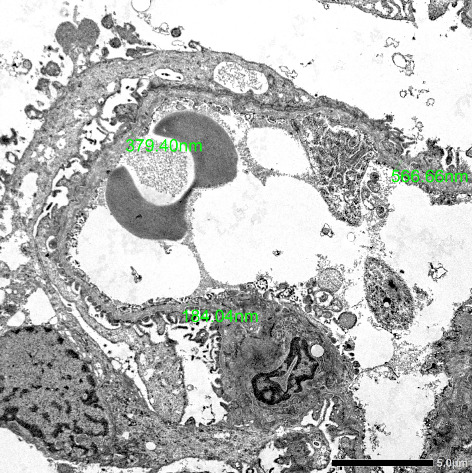

Introduction: Glomerulonephritis is a prominent cause of chronic kidney disease and encompasses a subset of renal diseases characterized by immune-mediated damage to the basement membrane, the mesangium, or the capillary endothelium. Symptoms in early stages are usually nonspecific and can be easily overlooked. Unfortunately, if not detected early, this may lead to end-stage renal disease. We present a case of a 23-year-old male patient with no family of kidney disease who had proteinuria on routine urinalysis. Case Presentation: A 23-year-old male, nonhypertensive and nondiabetic, with no family history of kidney disease coming in for proteinuria. During pre-employment checkup, patient was noted to have 4+ proteinuria on urinalysis. Creatinine was requested by company doctor with result of 1.05 mg/dL (eGFR: 104 mL/min/1.73 m2). Repeat urinalysis was done but still with 4+ proteinuria on urinalysis. Hence, advised consult with a nephrologist due to persistence of proteinuria. Upon consult, workups were done, which revealed hyperuricemia, urate crystals on urinalysis, persistence of 4+ proteinuria, and urine protein creatinine ratio of 2.8 (urine protein: 223.28 mg/dL and urine creatinine: 79.64 mg/dL). Patient was started on ACE inhibitor, hypouricemic agent, and advised kidney biopsy for further evaluation of proteinuria. The review of systems was pertinent for hearing impairment and blurring of vision. Kidney biopsy was done in which electron microscopy showed segmental podocyte foot process effacement. The glomerular basement membrane shows lamellation and alternate thickening and thinning. No definite electron-dense deposits are seen in glomerular basement membrane and mesangium. Mean glomerular basement membrane thickness is 299 nm (normal mean glomerular basement membrane thickness in adult males is 373 ± 42 nm). He was advised consult with an ophthalmologist and otolaryngologist. Regular checkup, monitoring of renal parameters, and appropriate medications were given. Conclusion: Although a rare cause of glomerulonephritis, Alport syndrome must be considered in patients presenting with subnephrotic range proteinuria and microscopic hematuria. Thorough history and physical examination and characteristic findings on kidney biopsy can help in the prompt diagnosis of the disease. Multidisciplinary care and early intervention can improve the quality of life and delay the progression to end-stage kidney disease among these patients.